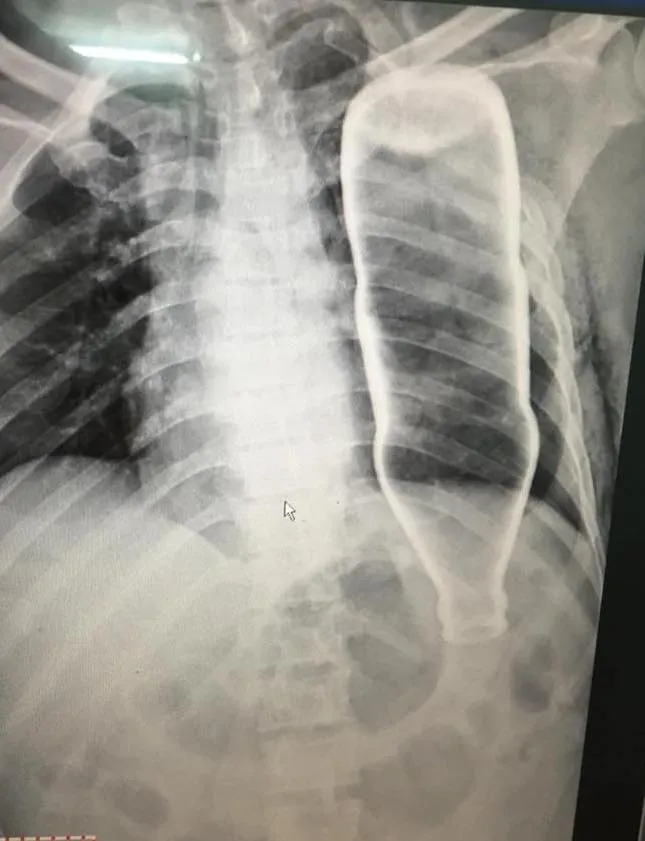

Chụp XQ, các bác sĩ phát hiện chai nước khoáng nằm gọn trong lồng ngực

Vỏ chai nước khoáng nằm trong lồng ngực của bệnh nhân